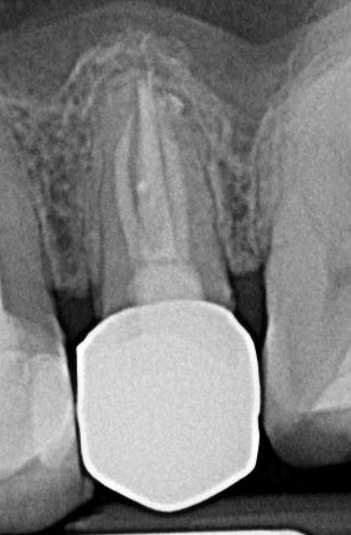

Caz 2 – Molar inferior cu șase canale

Un molar unu inferior care părea radiologic standard s-a dovedit, sub microscop, a avea șase canale, un caz extrem de rar. Fără magnificare, aceste canale nu ar fi putut fi detectate, ceea ce ar fi dus la recidivă cu probabilitate foarte mare.